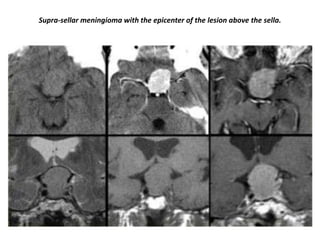

Supra-sellar meningioma with the epicenter of the lesion above the sella.

Sagittal images of the same case (Suprasellar meningioma) with the epicenter of the

lesion above the sella.

Supra-sellar meningioma with intra-sellar extension.